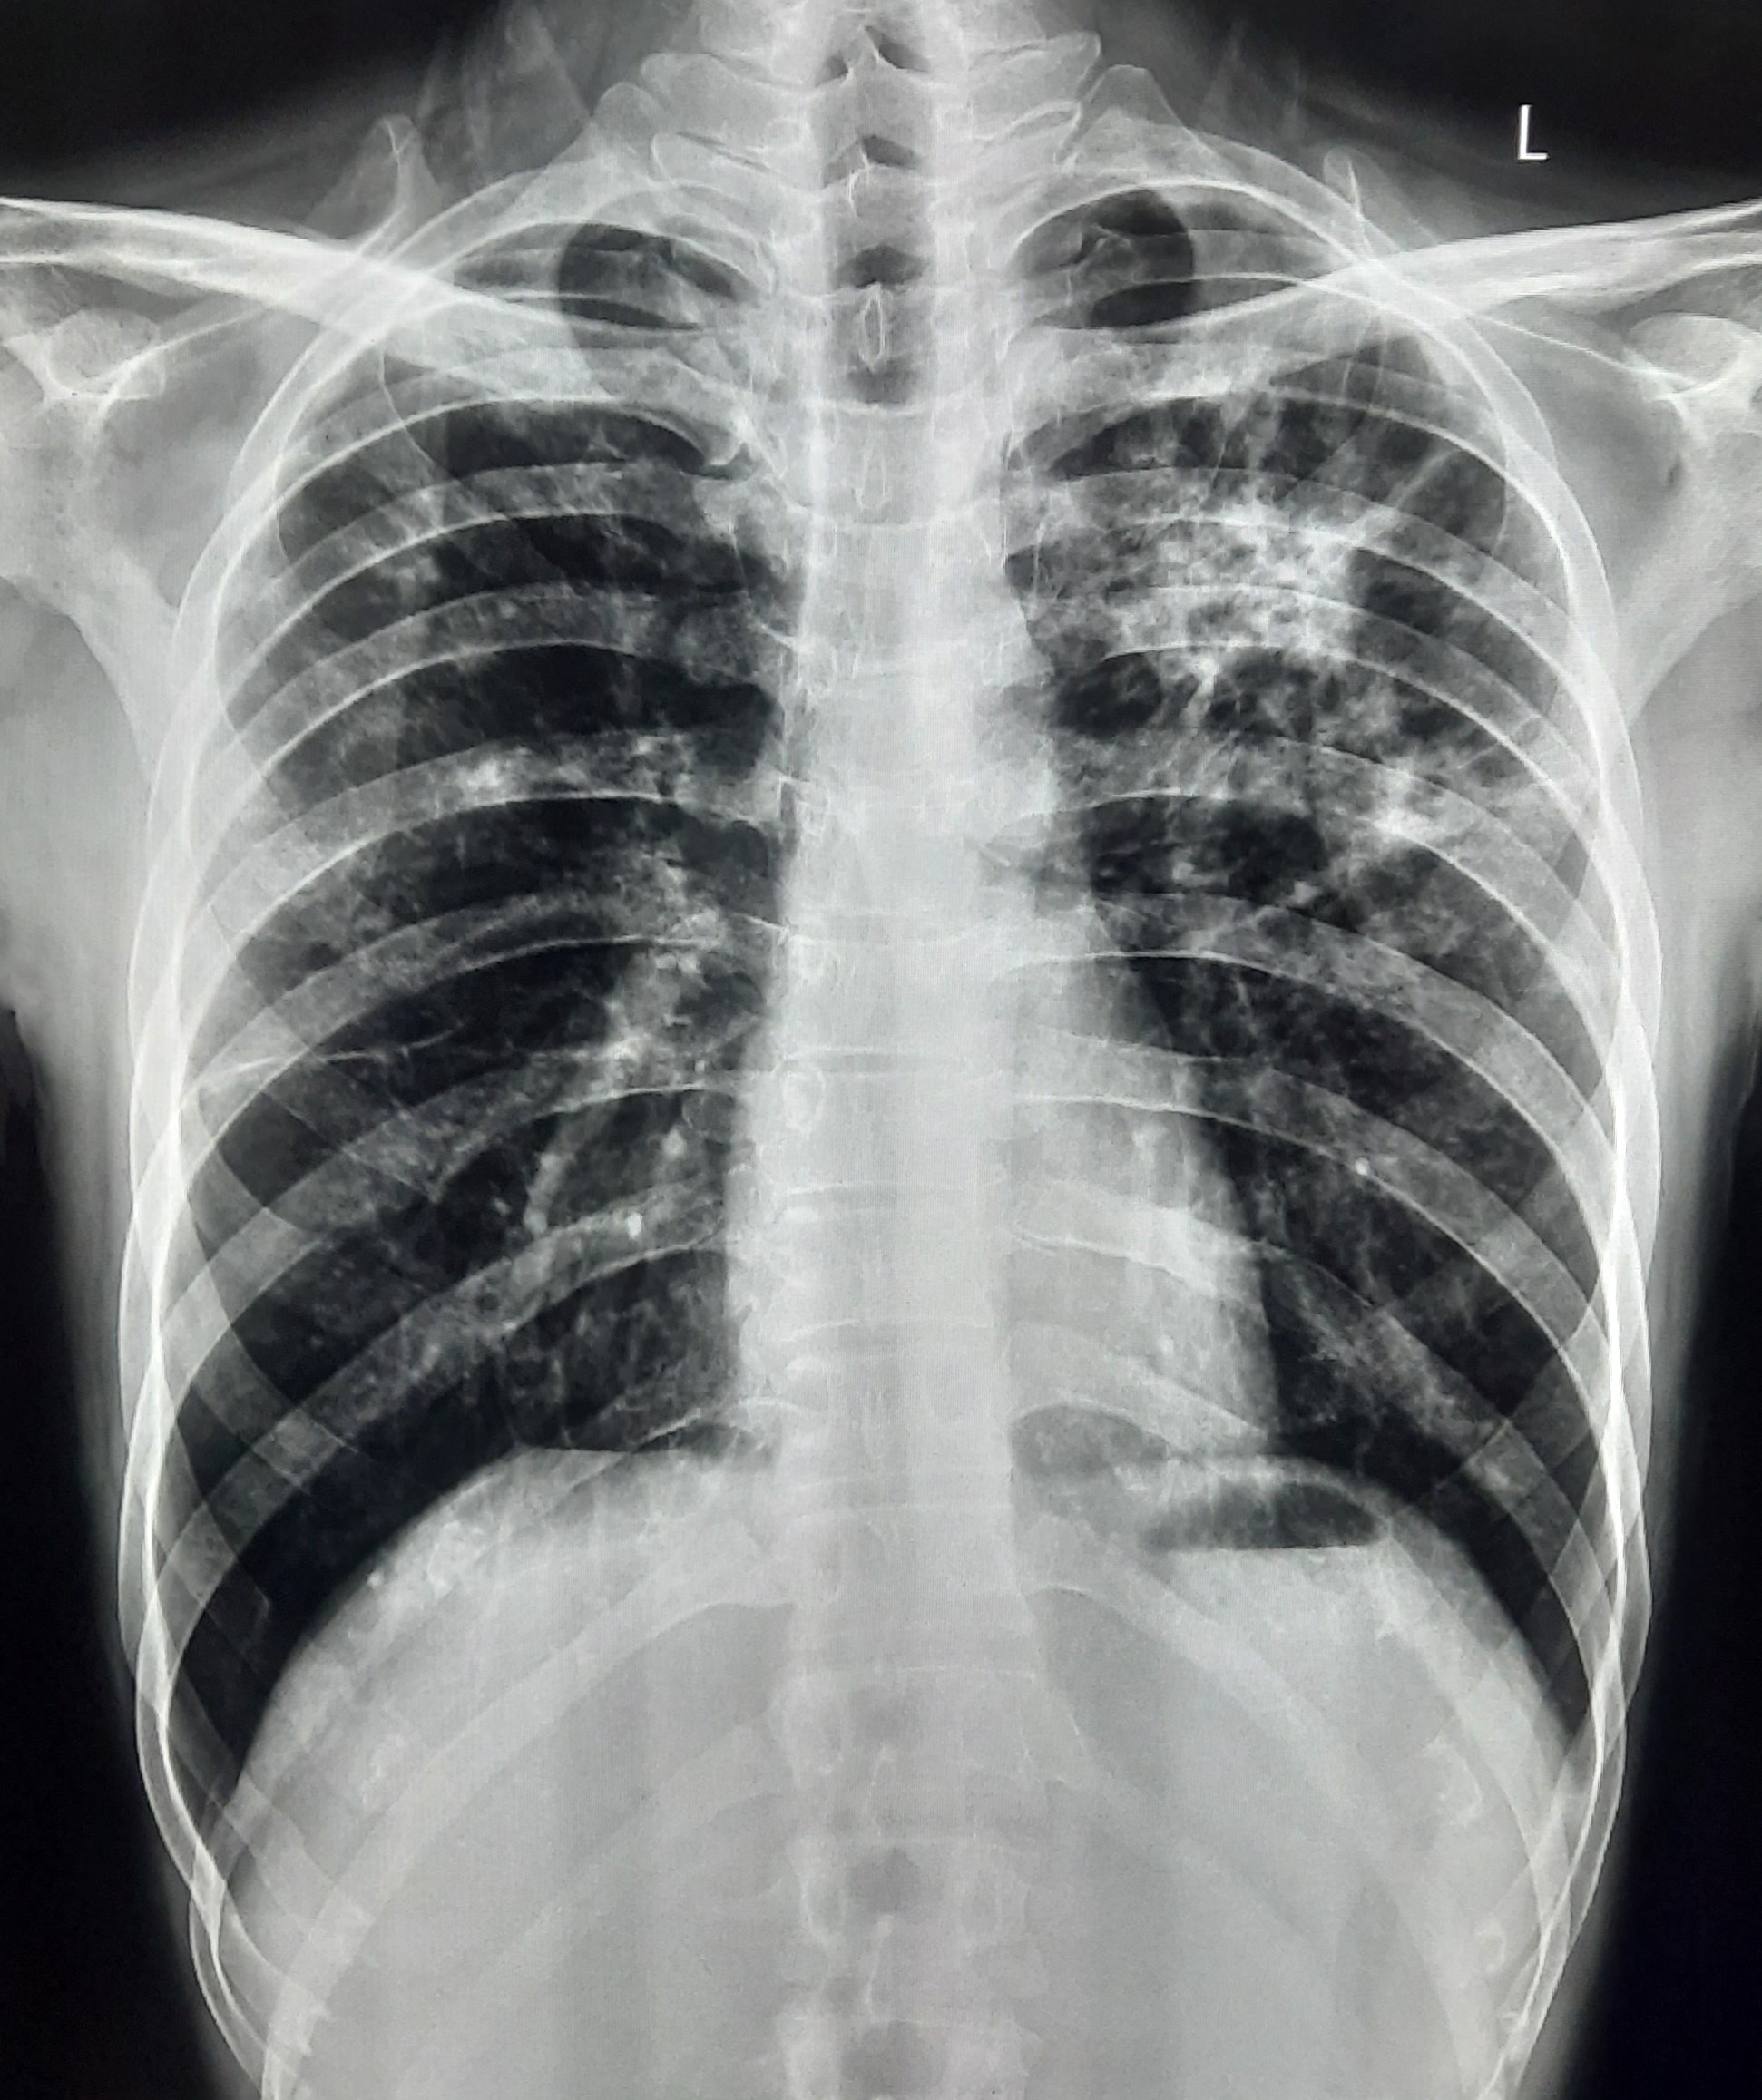

| 54 | IGGMC, Nagpur, Nagpur | P2 | 29-4418 | Pradip Bankar | Consent taken on Paper | 37 Yrs. |

Provisional Diag : Pulmonary Tuberculosis

Final Diag : Pulmonary Tuberculosis (Microbiologically Confirmed PTB) |

TB Case (Confirmed) | Left upper Zone Fibro cavitary lesion Present, Bilateral Lung Infiltration present | Abnormality visible on x-ray |